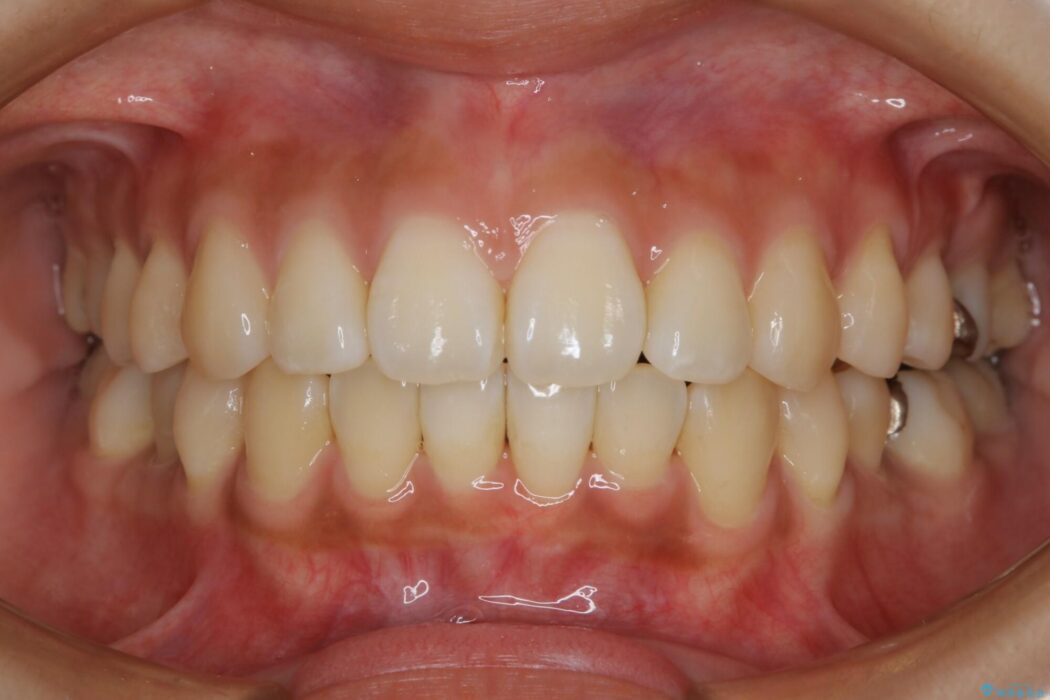

【20代女性】非抜歯でマウスピースの限界に挑戦する矯正治療

治療後について

患者様の意識も高く、しっかりとマウスピースを装着していただけたこともあり満足できる仕上がりとなりました。

本症例では最大量の移動もあり治療期間が掛かってしまいましたが、非抜歯でマウスピース矯正をしたいというご希望に応えることができました。